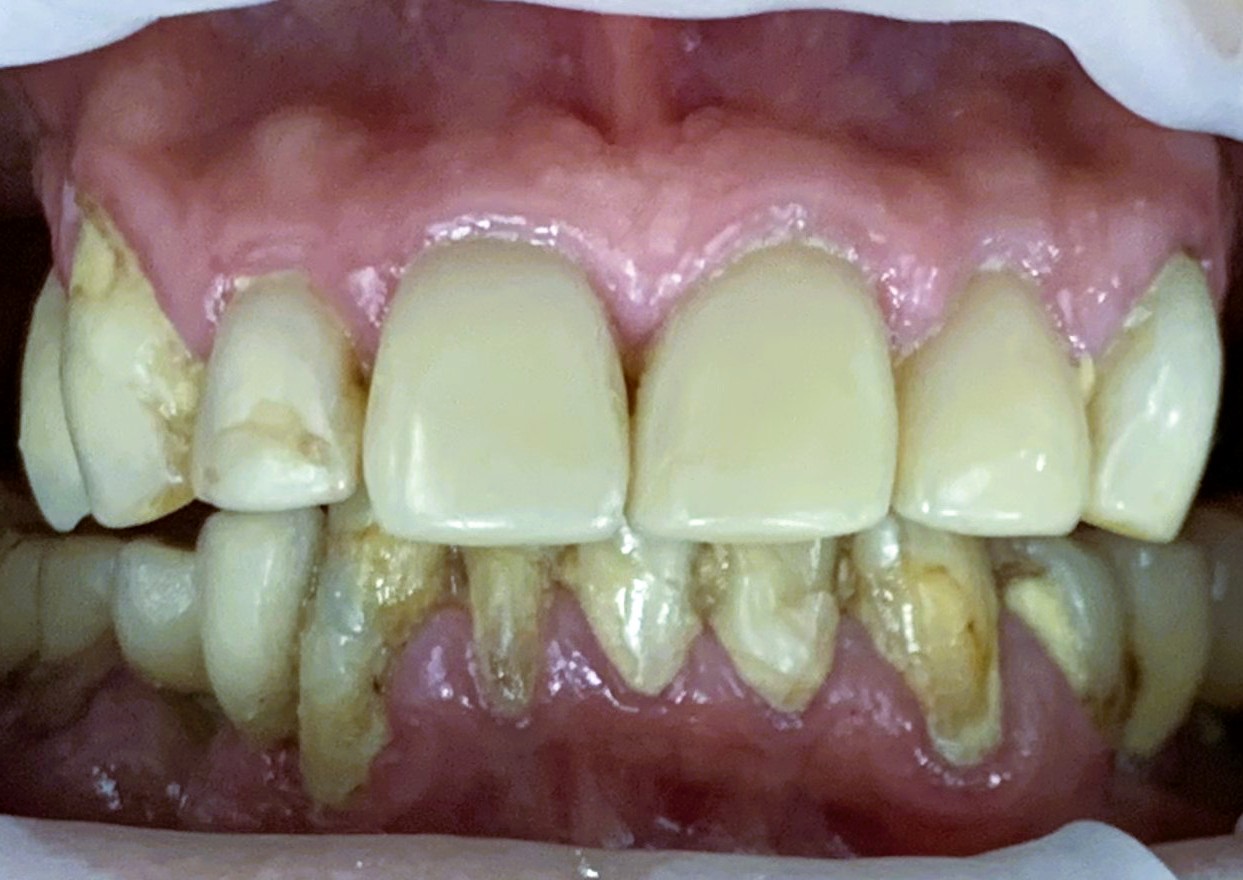

Жалобы: Острая жалоба в момент обращения на сломанные пломбы в области верхних центральных зубов (зубы 11, 21) в результате падения. Жалоба эстетического характера на внешний вид всех оставшихся зубов (13,12,11,21,22,23). Старый съемный протез верхней челюсти натирает десну и плохо держится.

- Пародонтит. Неудовлетворительная гигиена полости рта.

- Подвижность старых реставраций, сколы пломб, вторичный кариес.

- Рецессия десны 3–6 мм в области зубов 32–44.

- ИРОПЗ (индекс разрушения окклюзионной поверхности зуба) превышал 0,5–0,9

В данном клиническом случае продемонстрирован комплексный подход к лечению пациента с множественными стоматологическими проблемами: вторичным кариесом, сколами коронковой части зубов, необходимостью ортопедической коррекции. Лечение проводилось поэтапно, с учётом пожеланий пациентки и клинической целесообразности. Достигнут удовлетворительный функциональный и эстетический результат. Ниже мы наблюдаем счастливую улыбку довольного пациента.

И протез на верхней челюсти.